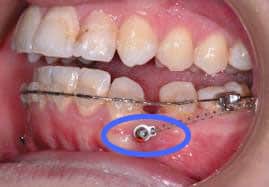

เป็นหมุดดึงฟันที่ทำมาจากวัสดุไทเทเนียม ออกแบบเป็นสกรูขนาดเล็ก เพื่อใช้ในการเพิ่มความสามารถในการเคลื่อนฟันให้เร็วกว่าวิธีการจัดฟันแบบปกติ มักใช้ในกรณีที่การจัดฟันแบบติดแน่นมีแรงไม่มากพอ ทันตแพทย์จะเลือกใช้หมุดนี้เพื่อช่วยดึงฟันเสริม จากการจัดแบบปกติ และเมื่อเสร็จสิ้นการรักษาจึงจะนำออก โดยหมุดดึงฟันนี้ไม่เป็นอันตรายต่อร่างกาย มีความปลอดภัยและได้มาตรฐาน